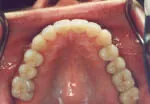

Composite fillings are tooth-colored restorations that are used in place of silver fillings on the chewing surfaces of back teeth. Unlike silver fillings made from metals that may cause further damage to teeth, these cosmetic fillings look extremely natural and typically require that far less of the tooth be removed.